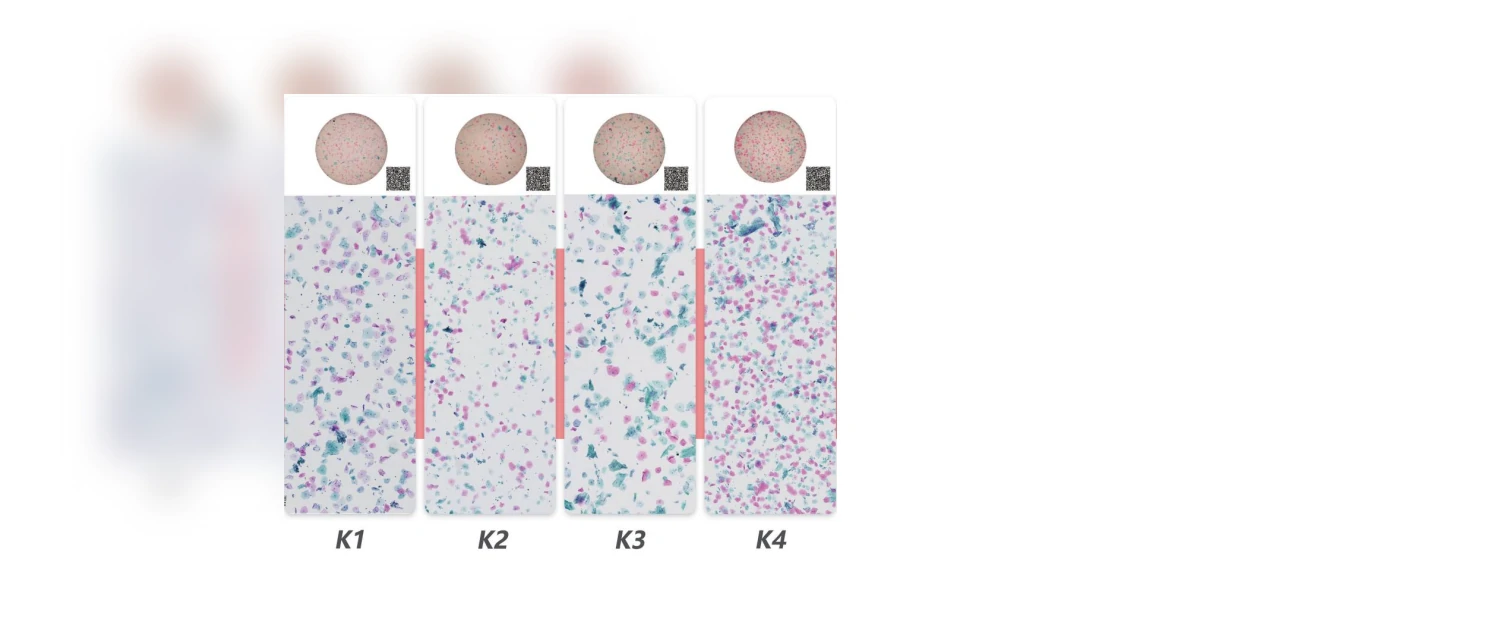

STAINING EFFECT

Equal cell distribution

Clear cytoplasm

Soft and beautiful color

Meet different visual preferences

| Papanicolaou Stain Solution |  | AI-specific staining solution Patented formula, high staining saturation, good sharpness High transparency, distinct spacing between cells and cell nuclei, clear and distinct cell clusters Effectively distinguishes between keratinized and non-keratinized cells Perfectly compatible with AI analysis and doctor's visual needs |